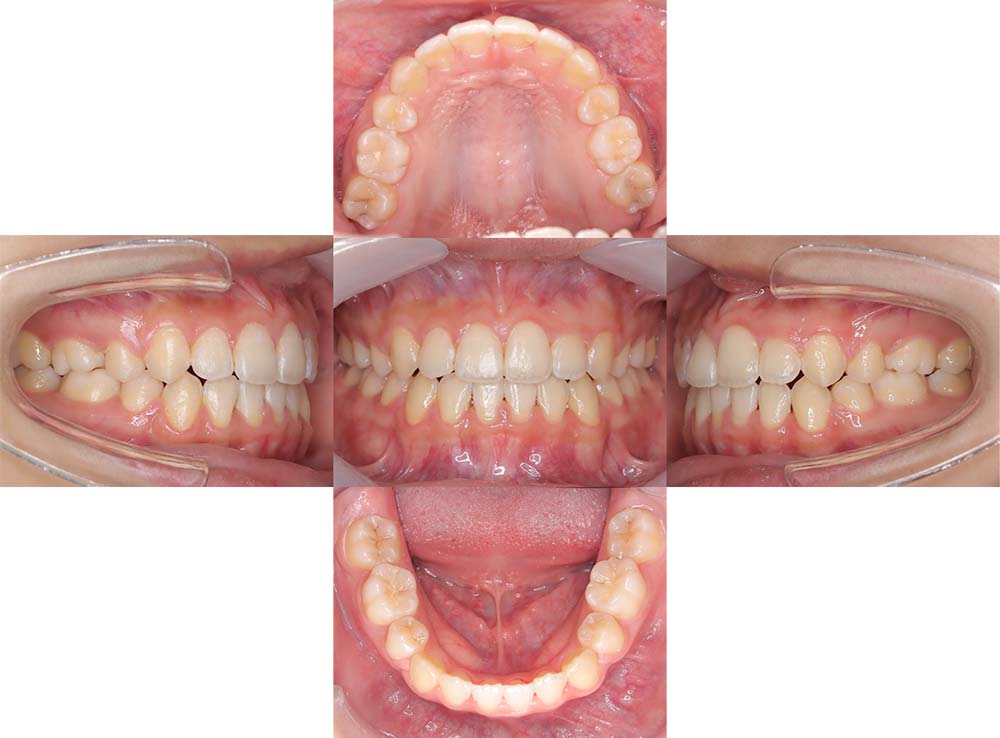

症例03

| 主訴 | 歯並びがガタガタしている。 |

| 診断名あるいは主な症状 | 過蓋咬合、叢生 |

| 年齢/性別 | 26歳・女性 |

| 矯正ステージ | 大人の矯正治療 |

| 治療方法 |

ワイヤー矯正 歯科矯正用アンカースクリュー(3本) |

| 抜歯部位/抜歯有無 | 抜歯 |

| 治療内容 | 上下顎の奥歯を後方に移動後、ガタガタの改善と上下顎前歯を後退させた。 |

| 費用 |

90万円程度(2025.10時点の料金となります。) ※矯正基本料金、アンカースクリュー、審美ブラケットを含む |

| 治療期間 | 2年8ヶ月 |

| 主なリスク・副作用 | 痛み、歯根吸収、歯肉退縮、虫歯、後戻り |